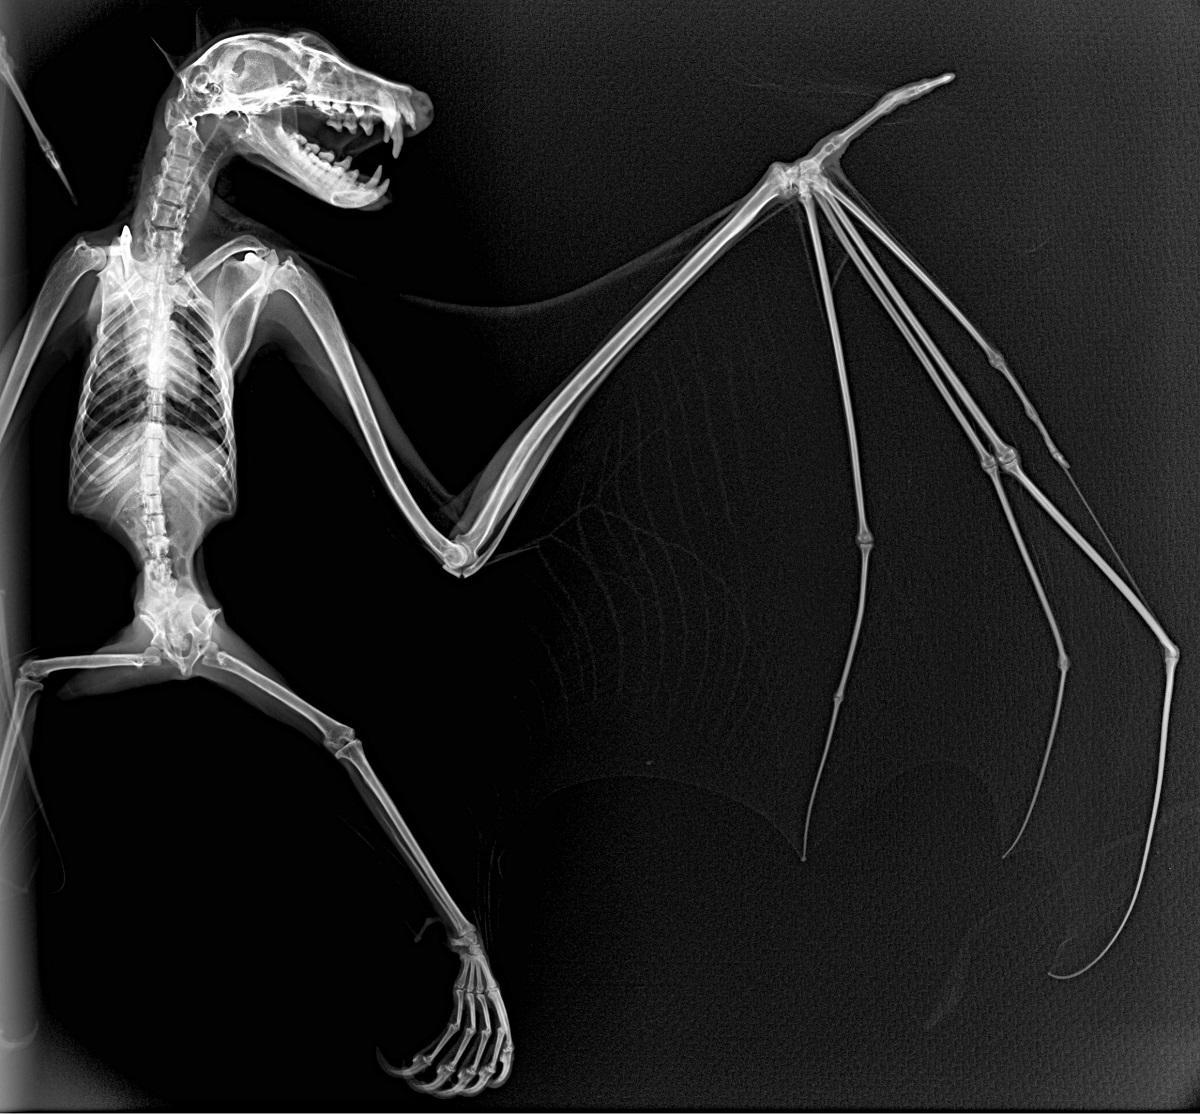

Radiografía de un zorro volador. / L. O.

Este procedimiento diagnóstico permite a estos expertos brindar una excelente atención médica. Al exponerlos a los rayos X, el equipo puede tomar fotografías de las partes óseas internas de los animales, comprobando la existencia de lesiones o enfermedades que a simple vista no podrían ser identificadas.